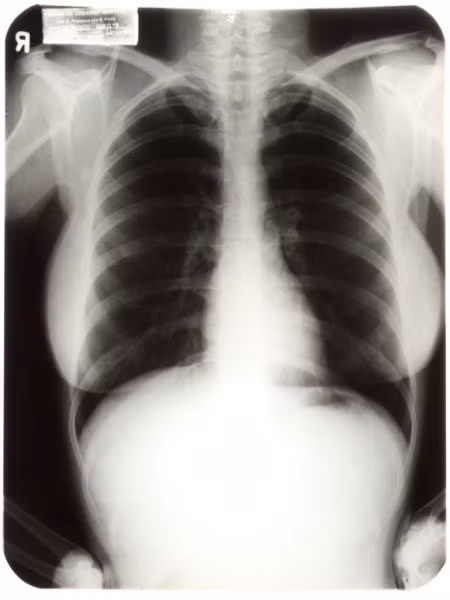

| Ảnh chụp X quang ngực của Marilyn Monre tại một bệnh viện năm 1954 được bán với giá 45.000 USD vào tháng 6/2010. |